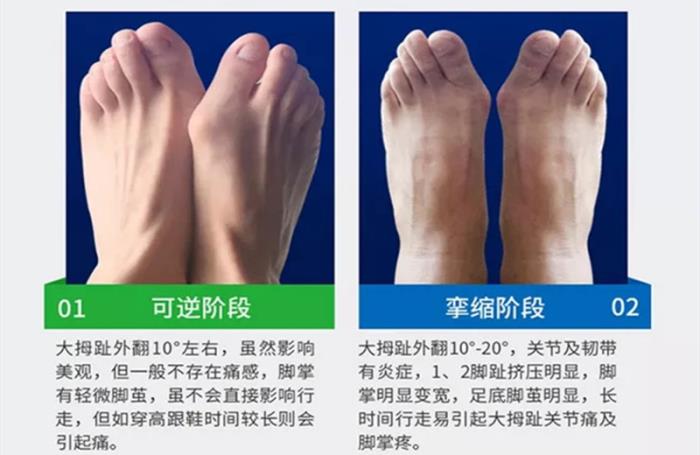

拇指外翻可分为四个阶段:

1.可逆阶段:大拇指外翻10度左右,没有疼痛感,脚掌有轻微脚茧,不会直接影响我们的行走。但是穿高跟鞋会引起疼痛感。

2.挛缩阶段: 大拇指外翻10-20度,关节及韧带有炎症,第一、第二脚趾明显挤压,脚掌明显变宽,足底脚茧明显,长时间行走易引起大拇指关节疼痛及脚掌疼痛。